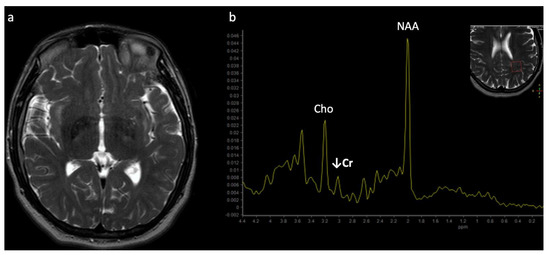

The most well-known and recognized pattern is Leigh syndrome (Figure 3) with symmetric deep grey nuclei and/or brainstem involvement on MRI [3]. Leigh syndrome may be due to a broad range of genetic variants in either nuclear or mitochondrial DNA.

Figure 3.

Leigh syndrome in a 10-year-old male with progressive right upper extremity weakness and left leg pain. (a) Axial T2WI shows T2 hyperintense necrotic lesions in the lentiform nuclei (arrows). (b) SV-MRS (short TE) over the basal ganglia shows increased Lac at 1.3 ppm consistent with anaerobic metabolism (indicating active on chronic disease, given the MRI appearance) and reduced NAA.